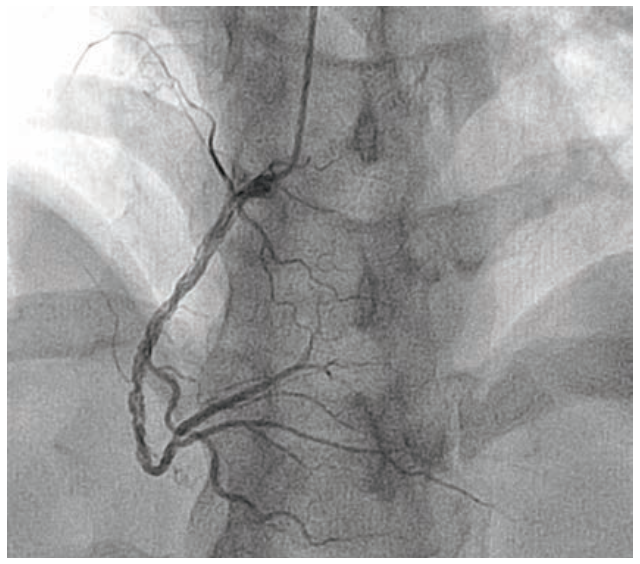

Coronary angiography demonstrated an unobstructed left main, and normal left anterior descending (LAD) artery and left circumflex (Figure 2). The right coronary artery (RCA) had an intraluminal defect extending from the ostium to the distal vessel (Figure 3, Video 1). Optical coherence tomography (OCT) was performed to further delineate this finding, and showed multiple channels with preserved intima and no evidence of plaque rupture (Figure 4, Video 2). Based on OCT, the diagnosis of woven coronary artery (WCA) was established. The decision was made to proceed with percutaneous coronary intervention (PCI) of the RCA with 3 overlapping drug-eluting stents from distal to proximal vessel (Figure 5). Post-PCI OCT was done and showed appropriate stent expansion. The patient was discharged on dual antiplatelet therapy (DAPT) in a stable clinical condition.

In our case, the mottled, hazy appearance of the RCA raised the possibility of dissection versus recanalized thrombus, based on angiography. Wiring can be particularly challenging given the multiple channels. As such, a hydrophilic guidewire with polymer coating (Hi-Torque Pilot 50, Abbott Vascular) was used, along with meticulous handling of the torque device, in order to negotiate the lesion safely. OCT was crucial to refute other diagnostic possibilities and establish the definitive diagnosis of WCA. Although WCA is usually considered a benign entity, acute coronary syndrome and even sudden cardiac death have been reported as possible sequelae.3 In our patient, the lesion extended from the ostial RCA to the distal vessel and before the bifurcation. Given the patient’s ongoing chest pain and rising cardiac biomarkers, PCI was warranted.